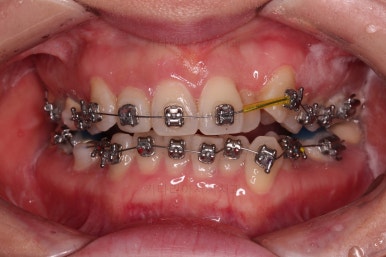

이번 환자분이 선택하신 장치는 엠파워 메탈이라는 자가결찰 금속장치인데요.

메탈장치라고 모두 구세대의 장치가 아니라 "자가결찰"인지 유무가 더 중요합니다.

즉, "자가결찰" 메탈이 "비 자가결찰" 세라믹보다 훨씬 우수한 장치입니다.

이렇게 젊은 여성분들도 메탕 장치를 많이 선택하시고요.

세람기이든 뭐든 교정하는게 뻔히 보이기 때문에 메탈을 부착한다고 해서 굳이 미적으로 더 마이너스이냐? 꼭 그런건 아닌 것 같습니다.

발치는 주로 장치 셋팅이 된 이후에 하게 되고요.

발치 공간이 줄어드는만큼 덧니가 가지런하게 될 공간이 생긴다고 보면 됩니다.

교정은 공간, 자리싸움 입니다.

치아가 가지런해지면서 이 뽑은 자리는 급속도로 줄어듭니다.

많이 삐뚤었던 앞니도 점점 좋아지는게 보이죠.

미니스크류를 이용해 주었고요.

그래야 중심선이나 입매에 더 도움이 되기 때문이죠.